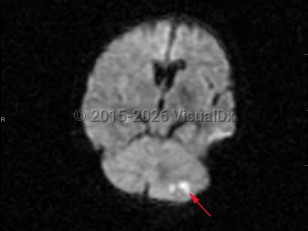

- Ischemic cerebellar strokes are predominantly either thrombotic or embolic. Thrombotic strokes are often caused by atherosclerosis, while embolic strokes are commonly cardiogenic (atrial fibrillation), septic, or due to coagulopathy.

- Hemorrhagic strokes can be intraparenchymal, due to hypertension, or secondary to subdural or subarachnoid hemorrhage.

Risk factors for cerebellar strokes are the same as for other cerebrovascular pathologies: hypertension, hyperlipidemia, diabetes, cardioembolic risks such as atrial fibrillation, and tobacco abuse are chief among them. Cerebellar hemorrhages can also be caused by a rupture of vascular malformations; hereditary hemorrhagic telangiectasia (HHT) is a particular risk factor. Rupture of vascular malformations is a more likely cause in children. Other risk factors for cerebellar hemorrhages include sympathomimetic abuse such as cocaine use. Increased urinary sodium is associated with increased risk.